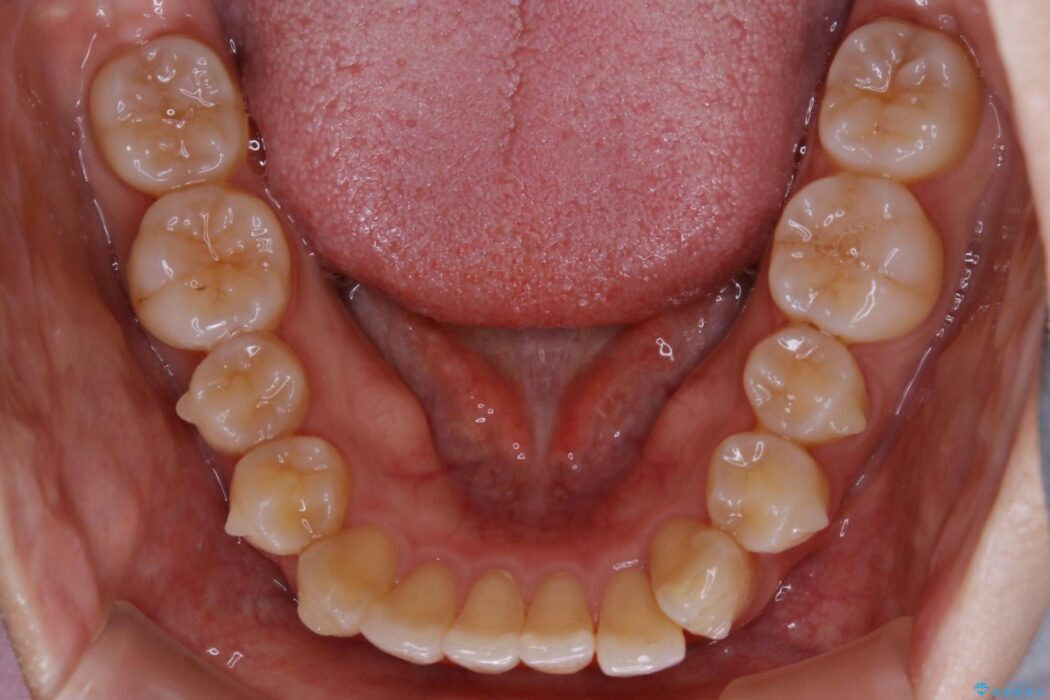

下の前歯のガタつきが気になるとご来院された患者様です。

インビザラインのライトパッケージにて、歯列拡大とディスキング(IPR)をを行いスペースをつくり非抜歯で治療を行いました。

ディスキング(IPR)

歯のガタつきをとるためのスペース作りの方法の一つにディスキング(IPR)という方法があります。

歯と歯の間を一ケ所あたり最大0.5mmまでの範囲内で削ることで歯自体が少し小さくなり、それにより作られるスペースを数ヶ所分合わせることで合計で数mmの大きなスペースが作れるという方法です。

当院ではなるべく歯の機能や見た目に影響の出ないよう、作業時に拡大鏡の使用や削るタイミングの微調整を行っています。